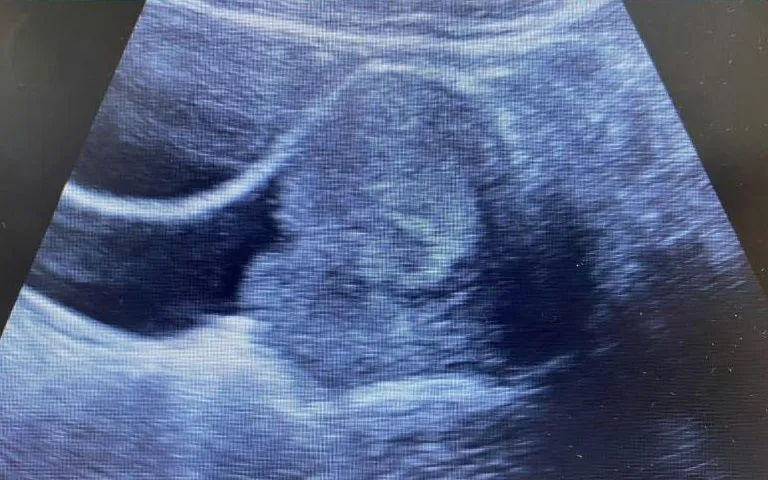

Xét nghiệm ban đầu ghi nhận nồng độ huyết sắc tố (Hb) chỉ còn 49 g/L - mức nguy hiểm có thể gây choáng, suy tuần hoàn nếu không can thiệp kịp thời. Siêu âm và thăm khám cho thấy khối hỗn hợp trong âm đạo kích thước 71x48 mm, gồm phần đặc - phần dịch, có tín hiệu mạch, chiếm gần toàn bộ lòng âm đạo và gây thiếu máu mạn tính.